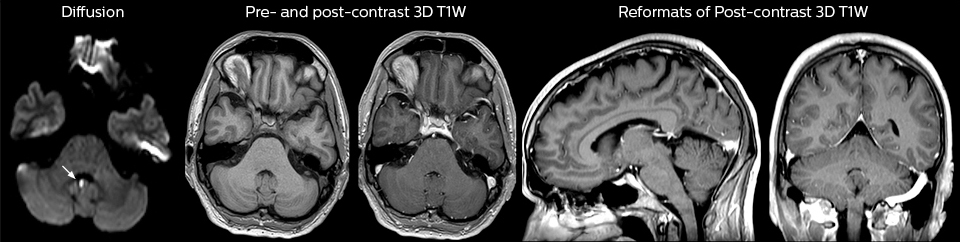

“We use mDIXON TSE extensively in our spine imaging in the emergency room,” says Dr. Karis. “It’s particularly nice in that it is very robust with regard to susceptibility type of problems that would come up with traditional spectral fat-saturated images; these problems are essentially eliminated with the mDIXON technique. In our ED environment it’s really nice to have the fat-free imaging that goes along with the mDIXON technique.

“For the thoracic and cervical spine routine non-contrast exam, for example, we perform one mDIXON T2 TSE sequence, which provides us with two outputs: the fat-and-water-together T2-weighted images, as well as the water-only sagittal T2-weighted images. And then we also perform an axial gradient echo exam.”

cervical spine mri in ed

Cervical spine routine exam

This patient presented with headache that was worse with neck flexion and we see a Chiari 1 malformation with low-lying cerebellar tonsils as well as some degenerative cervical thrombolytic change.